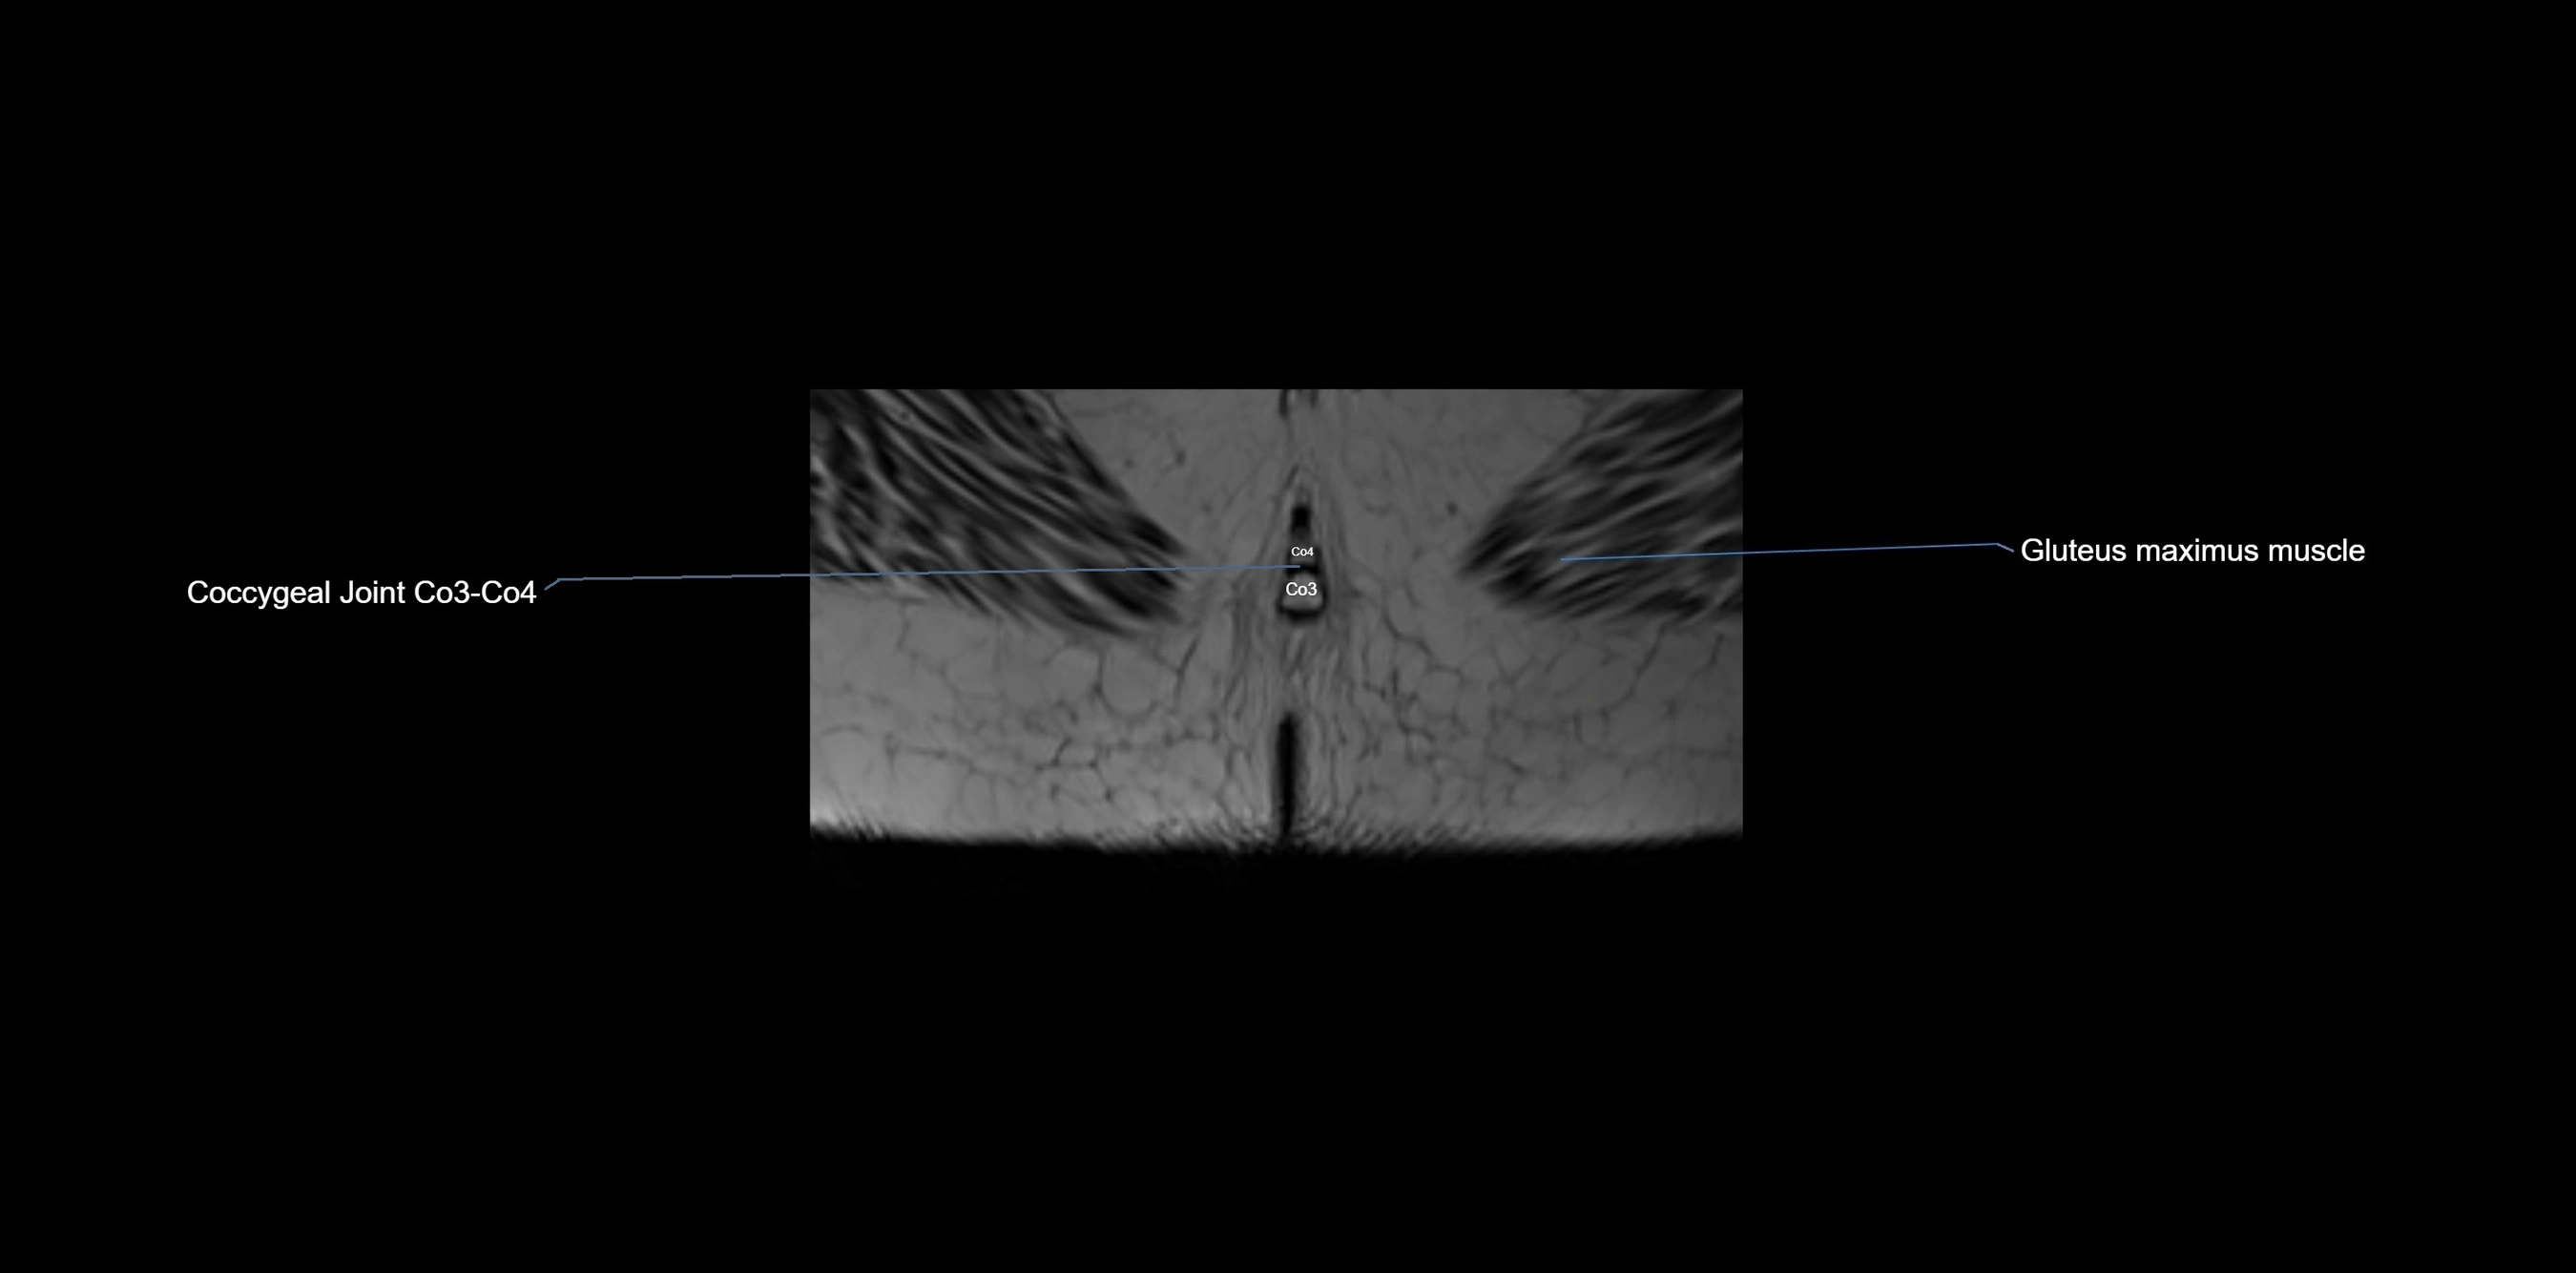

CT image

image